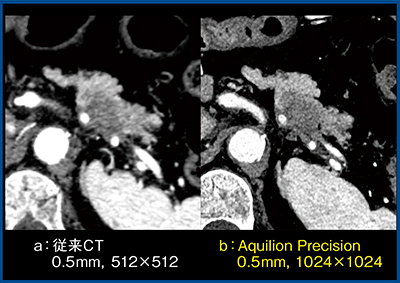

症例1は膵尾部がんだが,Aquilion Precisionでは従来CTとの比較で画像がよりシャープになっており,腫瘍の範囲などを評価しやすくなっている(図1)。また,Aquilion Precisionでは病変部の確認だけでなく,脾動脈および脾静脈への浸潤まで確信を持って診断できる。図2 cの斜矢状断像では,脾静脈は開存(↑)しているが,血管の内腔まで腫瘍が充満(↑)しており,さらに一部開存した部分(↑)やしっかりと開存している部分(↑)など,腫瘍と血管の位置関係がクリアに描出され,病理所見とも一致した。

図1 症例1:膵尾部がん